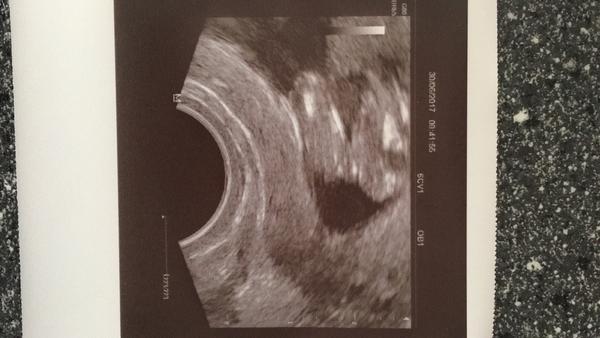

poznate podle fotky jestli je to holka ci kluk? 🙂

nejsem odbornik,ale rekla bych ze tak vidim kavove zrno,takze asi holka 🙂